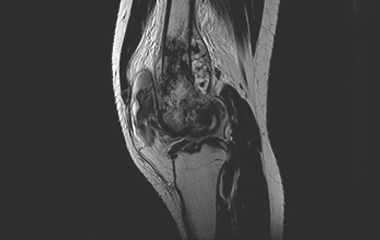

Conventional treatment of knee pain and resultant dysfunction currently does not adequately address the sources of pain due to difficulty visualizing, accessing and treating the intraosseous (bone marrow) lesion. Current clinical procedures and systems on the market only approximate the location of the lesion potentially providing a less precise clinical outcome as well as requiring fluoroscopy for localization and confirmation.

Management of early knee osteoarthritis presents a challenge for many orthopaedic surgeons and patients. Etiology from many of these patients originates from bone marrow lesions (subchondral edema) and if left untreated could lead to progressive pain, progression of arthritis, and subsequent need for knee arthroplasty(1).

The PanPlasty Instrument System is uniquely designed to precisely target and delivery biomaterials to ensure precise treatment of intraosseous lesions potentially lessening/alleviating patient pain and delaying the need for more complex and invasive arthroplasty surgical procedures.